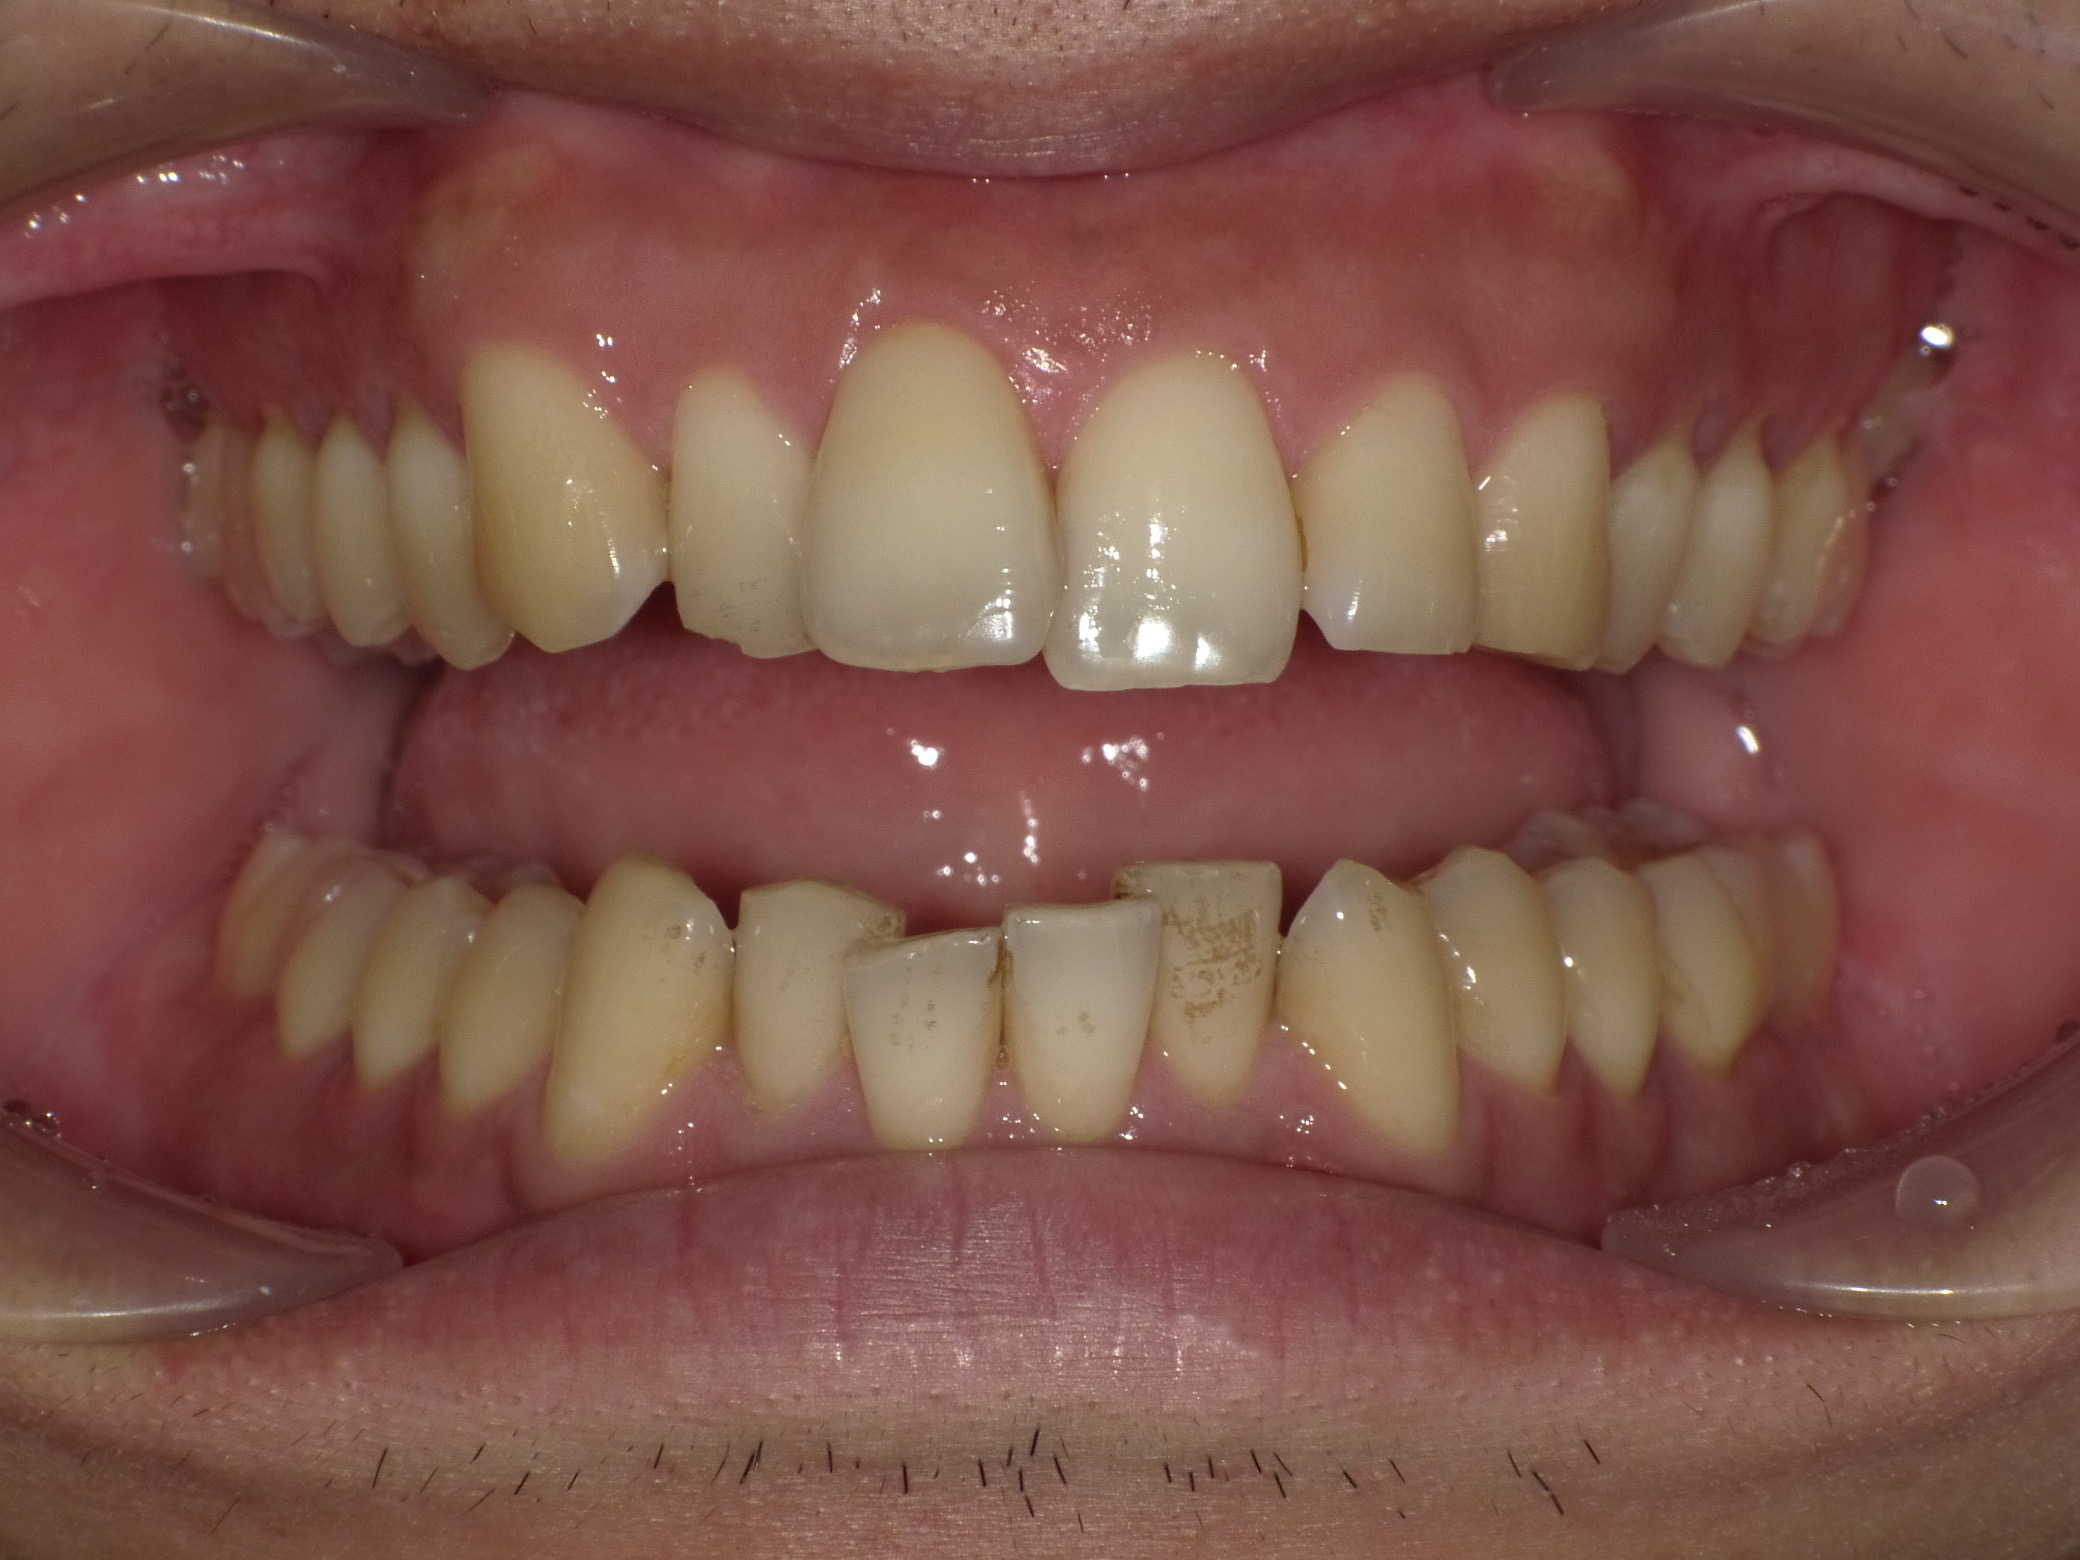

症例④

症例4_治療前 症例4_治療後

年齢・性別 24才男性

治療方法 ホワイトブラケット

治療期間 3年

治療総額 850,000円

特記事項 抜歯あり

リスク・副作用 治療の初期段階では痛みや不快感が生じやすくなりますが、1週間前後で慣れます